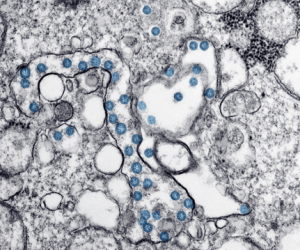

Novel Coronavirus (COVID-19)

You can help limit the spread of the Novel Coronavirus

The novel Coronavirus has been all over the news. The epicenter of the current outbreak was reportedly identified in December 2019 in Wuhan, China. We asked Cathy Fischer, Manager of Infection Prevention at CarolinaEast Medical Center, for her advice and she said, […]